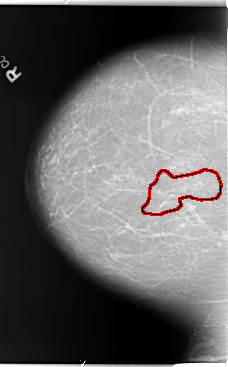

FILE: B_3011_1.RIGHT_CC.OVERLAY

TOTAL_ABNORMALITIES 1

ABNORMALITY 1

LESION_TYPE CALCIFICATION TYPE PLEOMORPHIC-FINE_LINEAR_BRANCHING DISTRIBUTION LINEAR-SEGMENTAL

ASSESSMENT 5

SUBTLETY 3

PATHOLOGY MALIGNANT

TOTAL_OUTLINES 1

BOUNDARY